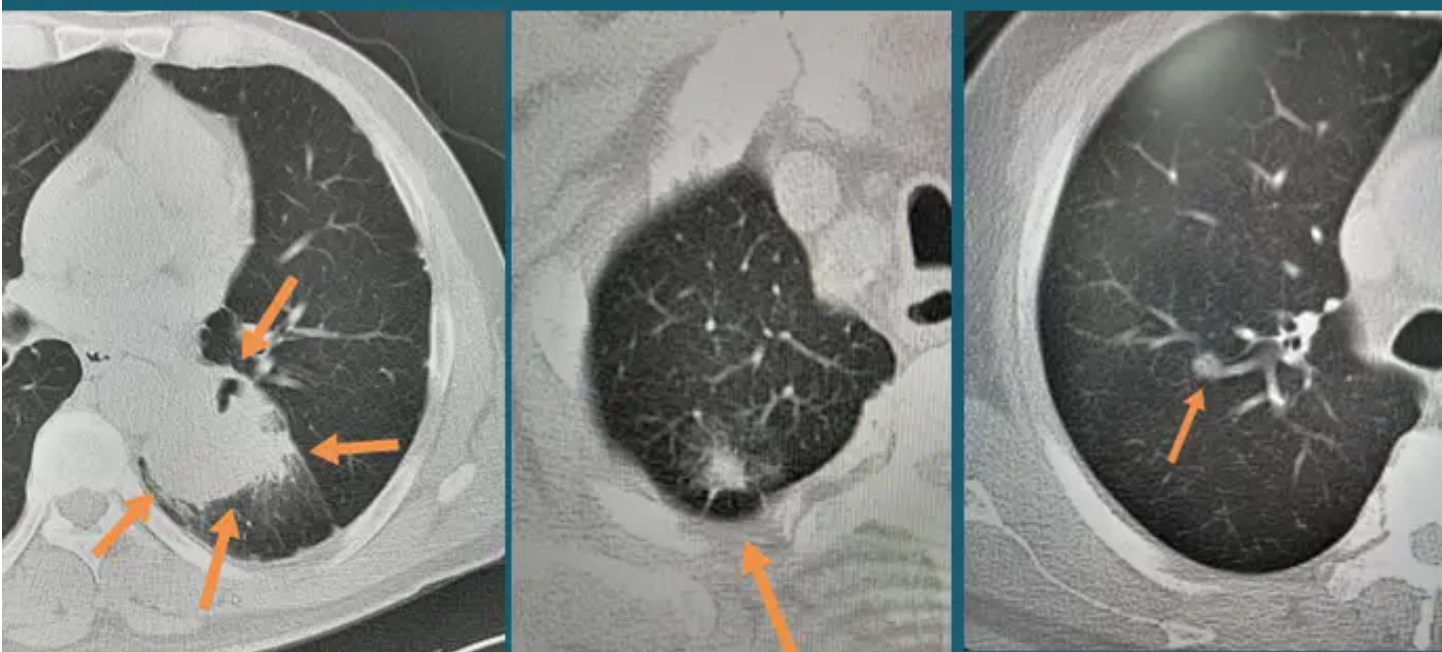

肺结节分为实性结节、纯磨玻璃结节和混合磨玻璃结节三种类型。其中混合磨玻璃结节恶性程度最高。

1) 结节大小 直径﹥15mm的实性结节,或直径﹥8mm的混合磨玻璃结节。

2) 结节形状 结节长得越不规则,恶变可能性越大,比如结节有分叉、毛刺、空洞等。